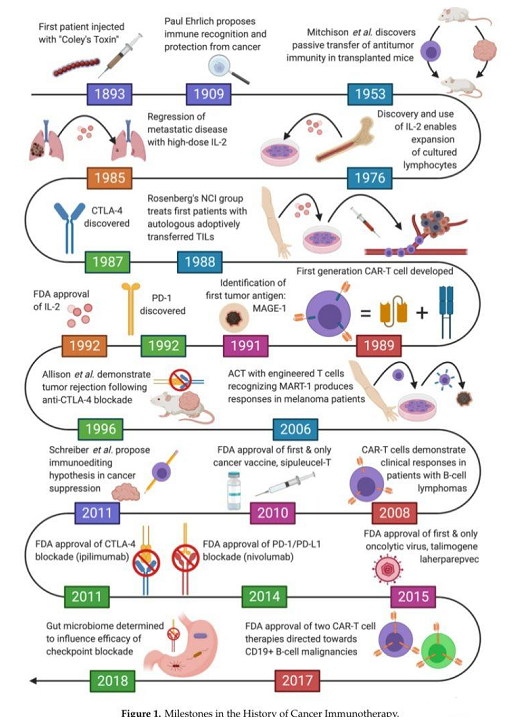

其實,免疫療法的歷史已經(jīng)有了百年,而人們真正認識它卻是近幾年的事,尤其是當國內(nèi)第一款CAR-T細胞藥物上市后,人們對于免疫細胞療法的期待越來越高。

因此如何喚醒體內(nèi)T細胞、提高T細胞的活性來對抗癌細胞就成為了國內(nèi)外醫(yī)學(xué)研究者們研究的主要方向。目前,基于T細胞的免疫療法主要有CAR-T療法、TCR-T療法等。

CAR-T療法

CAR-T細胞療法,全稱是嵌合抗原受體T細胞免疫療法(chimeric antigen receptor T cell,CAR-T),是應(yīng)用患者自身的T淋巴細胞,經(jīng)過實驗室重新改造,裝載上具有識別腫瘤抗原的受體及共刺激分子,體外擴增后再次回輸入患者體內(nèi),從而識別并攻擊腫瘤細胞。

簡單來說,是將患者體內(nèi)的T細胞提取出來,在體外人為地裝上嵌合抗原受體(CAR)——相當于給T細胞裝上一個GPS導(dǎo)航系統(tǒng),讓T細胞能夠找到腫瘤、消滅腫瘤。在血液腫瘤領(lǐng)域,與手術(shù)、放療、化療等傳統(tǒng)治療方式相比,CAR-T具有治療更精準、殺瘤范圍廣、治療次數(shù)少、作用時間長、副作用輕等優(yōu)勢。

TCR-T療法

TCR-T療法是一種過繼免疫細胞療法(Adoptive Cell Transfer Therapy,ACT)。過繼免疫細胞療法是指從腫瘤患者體內(nèi)分離免疫活性細胞,在體外進行擴增和功能鑒定,然后向患者回輸,從而達到直接殺傷腫瘤或激發(fā)機體的免疫應(yīng)答殺傷腫瘤細胞的目的。

TCR-T細胞和CAR-T細胞都屬于經(jīng)基因工程技術(shù)改造的T細胞。相較于CAR-T療法,TCR-T療法在實體瘤治療領(lǐng)域具備獨特優(yōu)勢。TCR-T細胞療法可識別細胞膜表面或細胞內(nèi)來源的腫瘤特異性抗原,已從最開始的基礎(chǔ)免疫研究走進臨床應(yīng)用,在實體瘤中顯示出初步療效,成為目前最有可能在實體瘤領(lǐng)域中取得突破的T細胞免疫療法。